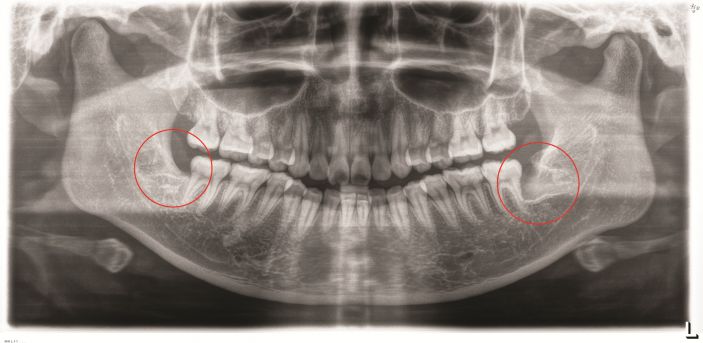

△阻生智牙。

△智牙拔除前。